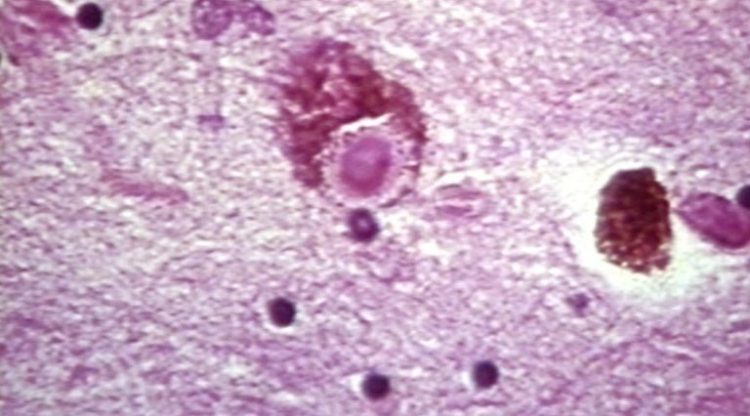

Jest to wirus przejmujący kontrolę nad systemem nerwowym zarażonego i “manipuluje” procesami neurologicznymi aby móc się szybciej rozprzestrzeniać. Zarażeni mają halucynacje, są agresywni a w zaawansowanych stadiach choroby zaczynają bać się wody. Tak opisuje wściekliznę Melvin Sanicas, lekarz zajmujący się zdrowiem publicznym i wakcynolog.

Wirus wścieklizny powoduje powstanie chęci gryzienia różnych rzeczy. Po objawieniu sie symptomów w przeważającej części skutkuje śmiercią.